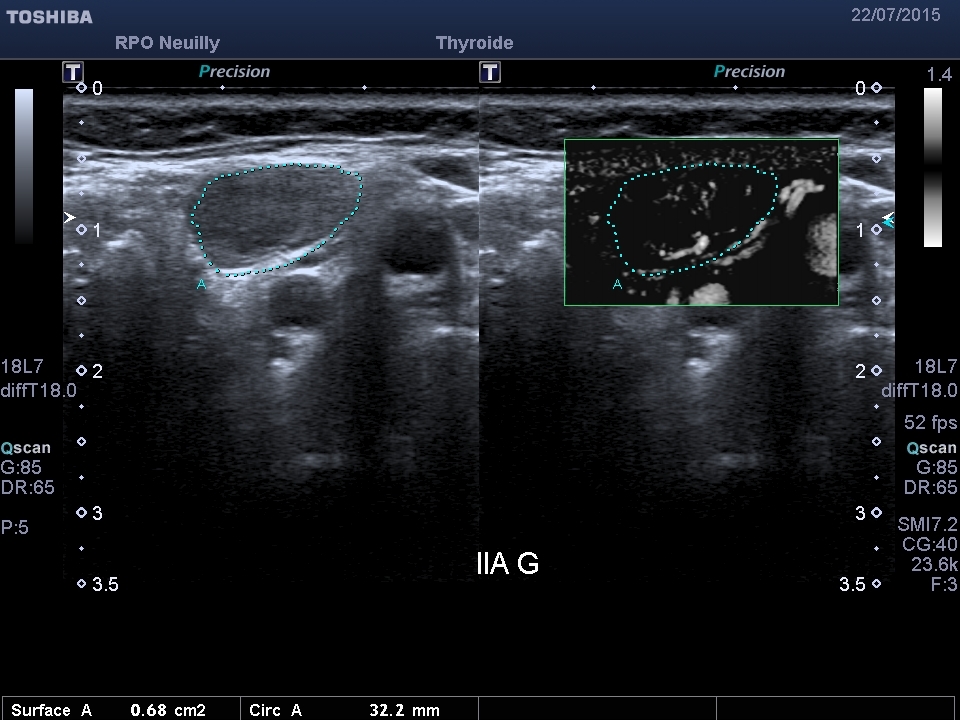

Dr J.T.: Depuis que je travaille avec cette technique, j’utilise beaucoup les deux modalités de SMI. J’ai commencé par le c-SMI (Fig.1) qui a l’avantage de donner les informations tissulaires et vasculaires fusionnées et qui permet donc de bien voir où se situent les vaisseaux par rapport au ganglion. J’ai ensuite travaillé avec le m-SMI (Fig.2), en utilisant la double image et en plaçant la zone d’intérêt (ROI) sur l’image tissulaire pour avoir sur l’image m-SMI les contours du ganglion. Je me suis rendu compte que ce mode est encore plus sensible, en particulier à la périphérie du ganglion dans cet exemple où l’on recueille du signal supplémentaire.